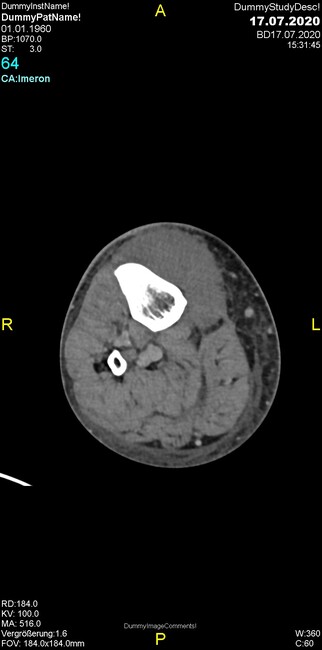

Um welche Modalitäten handelt es sich?

- Röntgen p.a. und lateral, CT coronar Knochenfenster, CT axial Weichgewebsfenster

Was fällt in der Projektionsradiographie auf?

Was fällt in der CT im Knochenfenster auf?

- Osteolyse der Tibiametaphyse unter Beteiligung der Kortikalis

Was kommt differentialdiagnostisch in Frage?

- Osteomyelitis mit Weichgewebsanteil

- Metastase mit pathologischer Fraktur